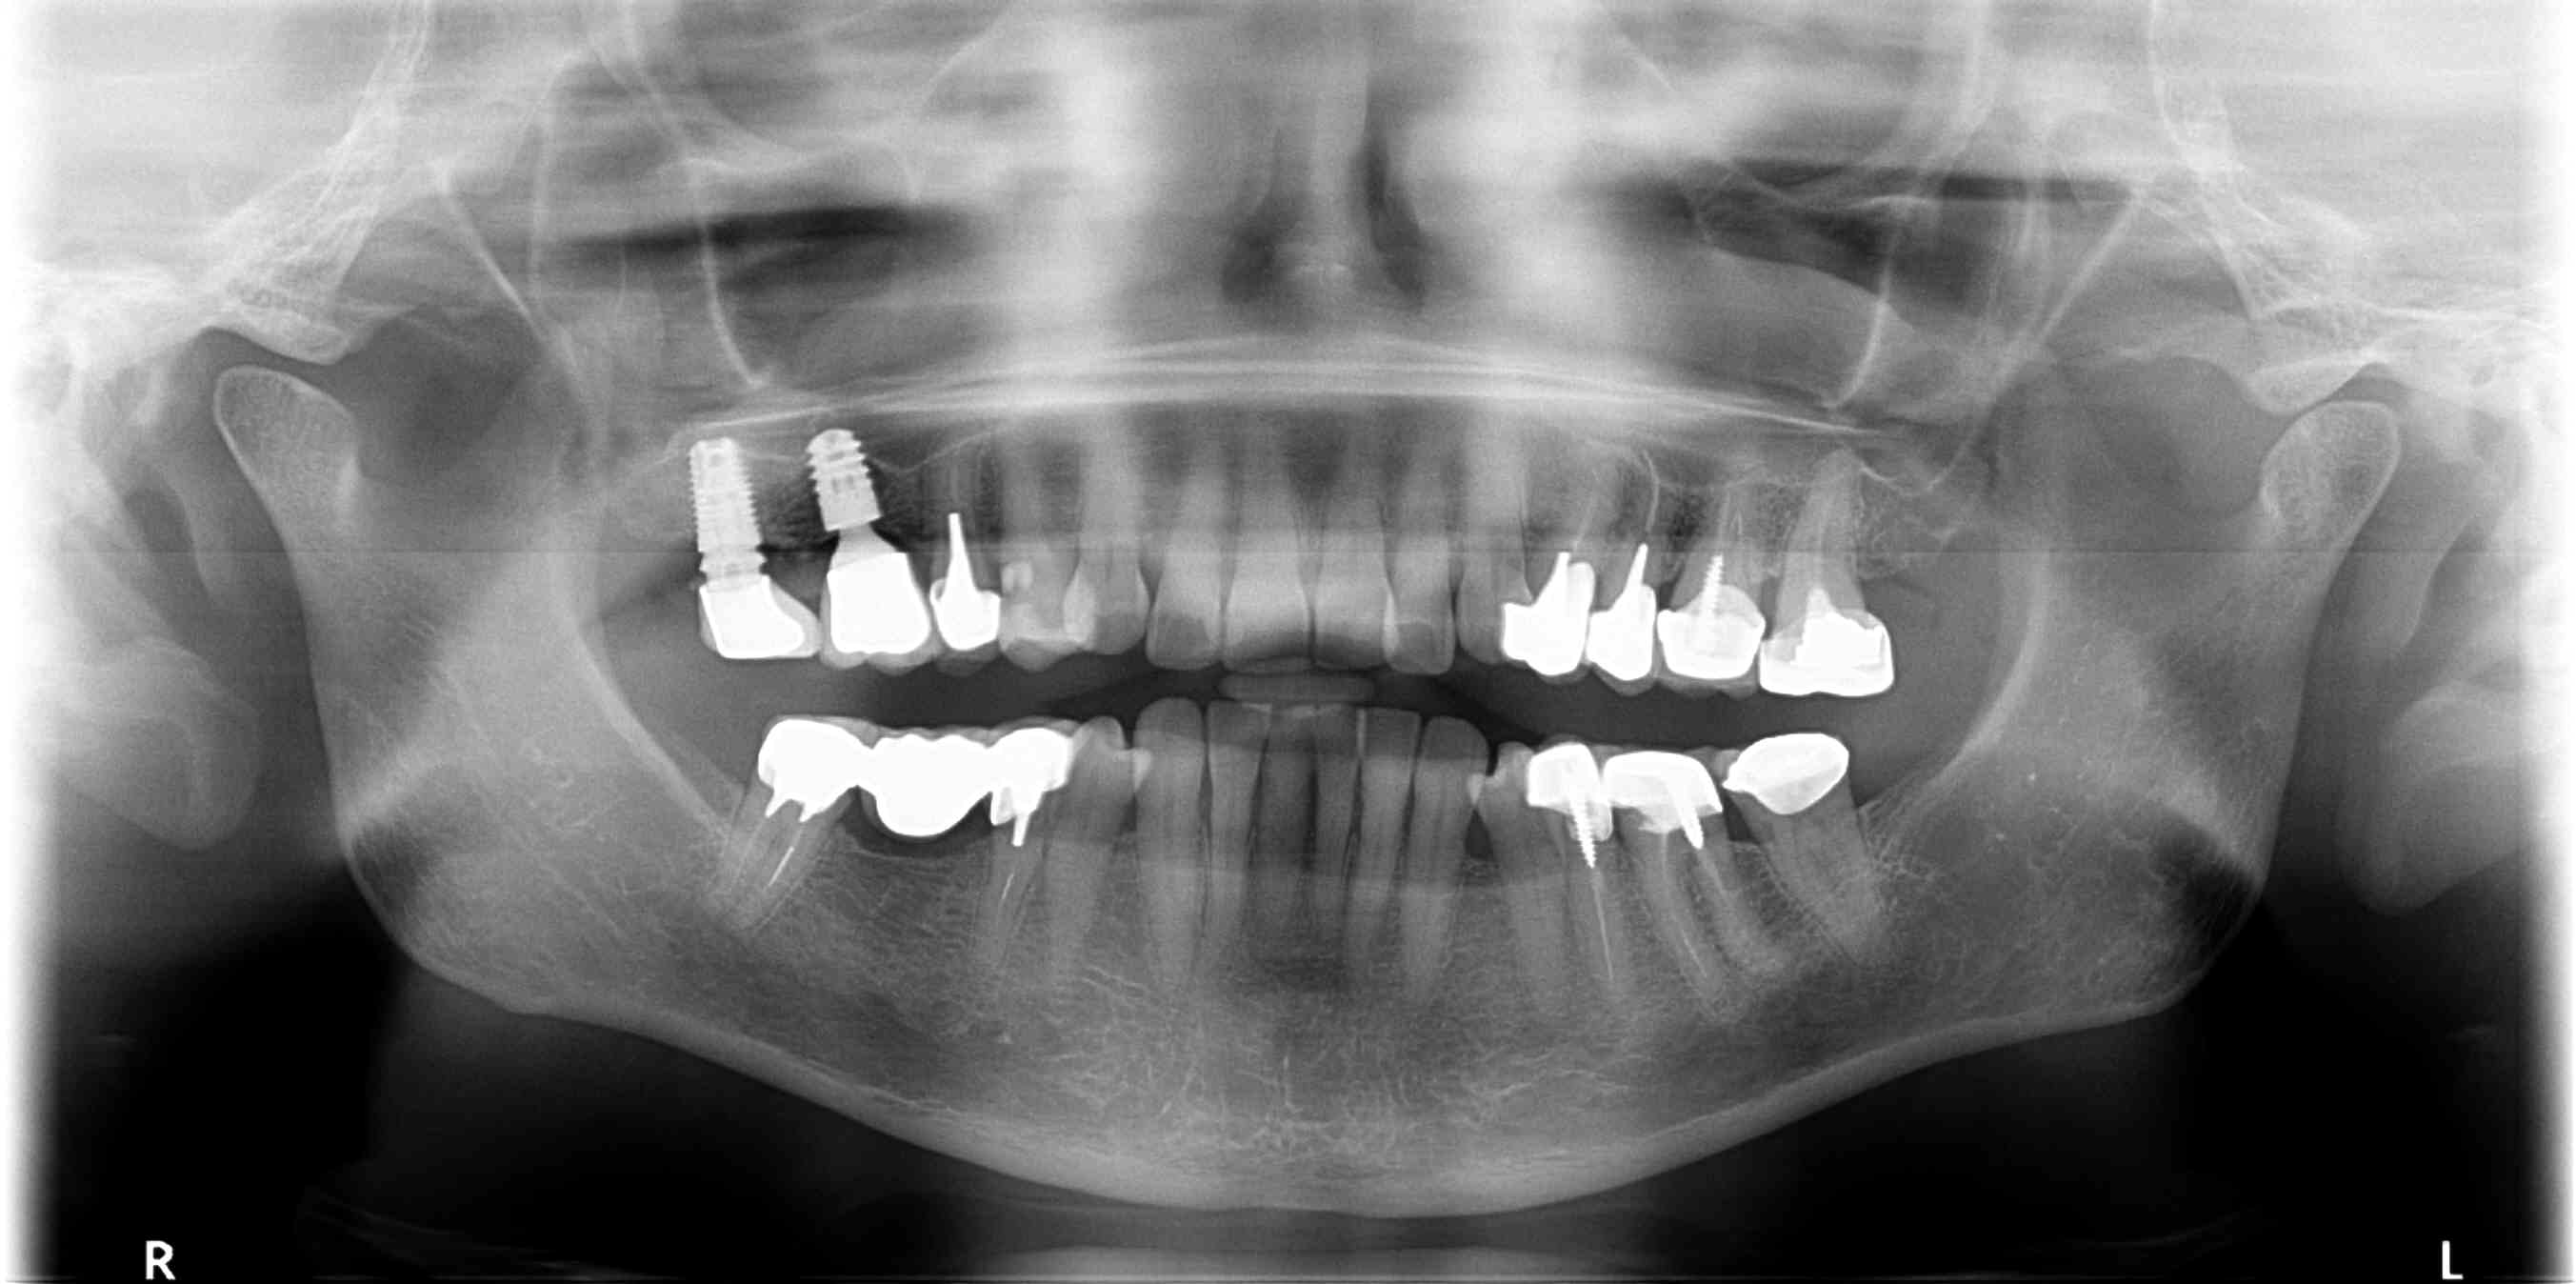

Xmareewp3u8dpxysw9yijemkwckn - Eugenol

Bonne gueule de 3i…..

Maintenant ta radio n’est pas super contrastée…mais à 90% c’est un osseotite certain tapered